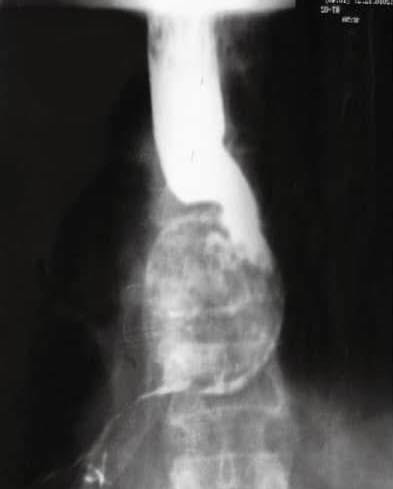

Phim chụp X-quang cho thấy một con giun tròn lớn đang quằn quại trong thực quản của người phụ nữ. Nguyên nhân được xác định là do món ăn ưa thích của bà.

Cụ thể, một phụ nữ 70 tuổi bị khó nuốt liên tục trong 4 năm. Lần này tình trạng nghiêm trọng hơn nên bà đã đến bệnh viện. Bác sĩ cho uống barium rồi chụp X-quang, phát hiện vật thể lạ cuộn thành vòng trong thực quản. Vật thể đó là giun đũa Ascaris lumbricoides.

Một phụ nữ 70 tuổi gặp khó khăn khi nuốt. Chụp X-quang phát hiện một con giun lớn.

Tại bệnh viện, mọi thứ đều bình thường. Bác sĩ đã chỉ định tôi làm xét nghiệm nuốt bari, một chất cản quang. Phim chụp X-quang cho thấy một khối hình xoắn ốc trong thực quản, như thể nó đang chặn đường đi, nhưng chất cản quang vẫn có thể đi qua. Bác sĩ đã tiến hành điều trị ban đầu và chuẩn bị cho bệnh nhân nội soi (EGD).